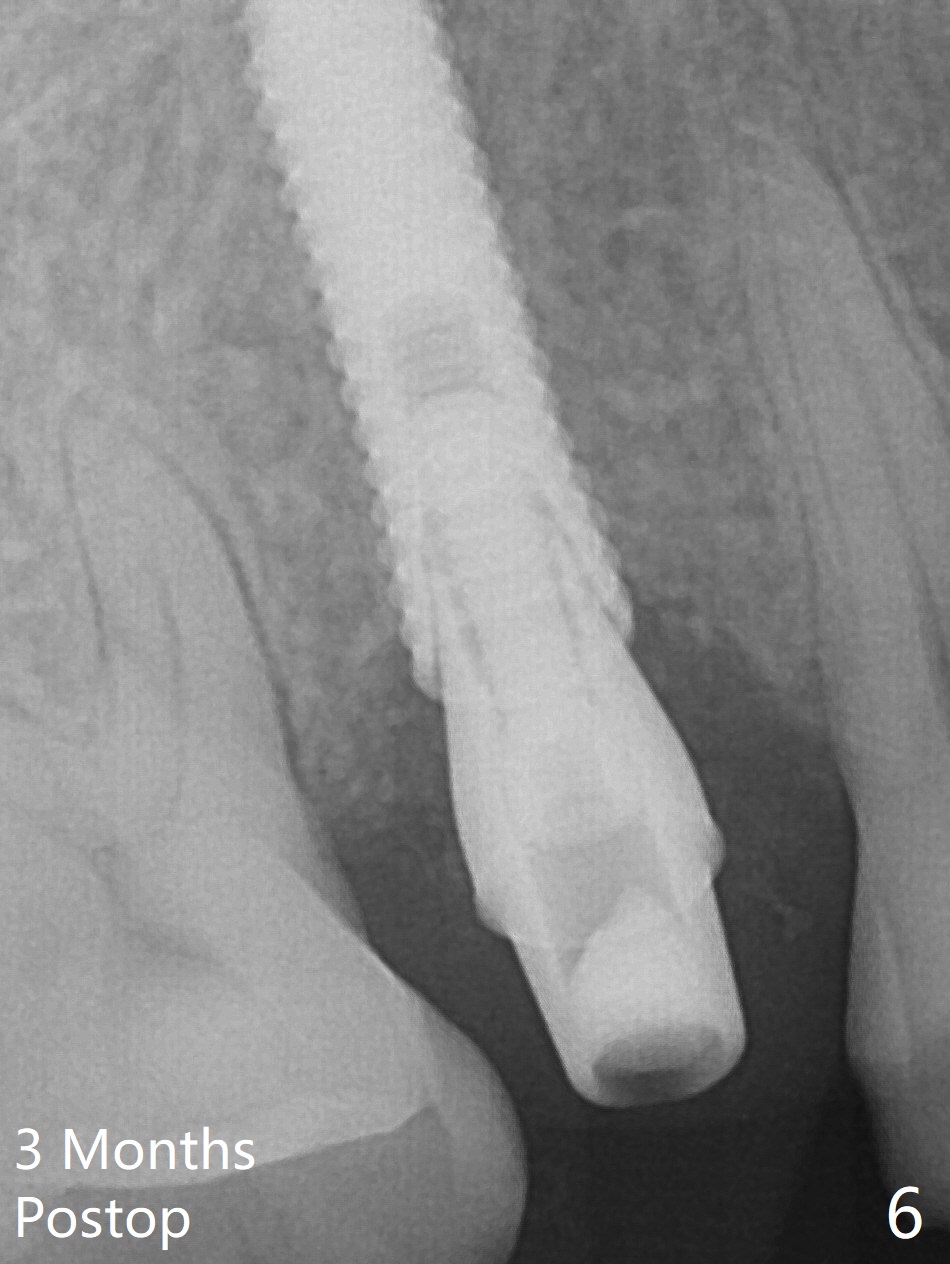

A 61-year-old man cracks the tooth #4 while chewing on a piece of chicken bone (Fig.1,2). Initial osteotomy appears to be able to hold a 16 mm long implant (Fig.3). After sequential osteotomy, a 4x16 mm implant is initially unable to be seated low enough for the buccal crest. Following packing the osteotomy with Vanilla Graft (.5-1 mm) and additional 2-3 mm depth of osteotomy, the implant is placed slightly apical to the buccal crest (Fig.4,5); with placement of Vanilla Graft (*) and a 4.5x4(4) mm abutment, an immediate provisional is fabricated to close the socket. The provisional is removed 3 months postop because of poor local oral hygiene (Fig.6,7). The gingiva is healthy 2-3 weeks later; it is easy to take impression (Fig.8).